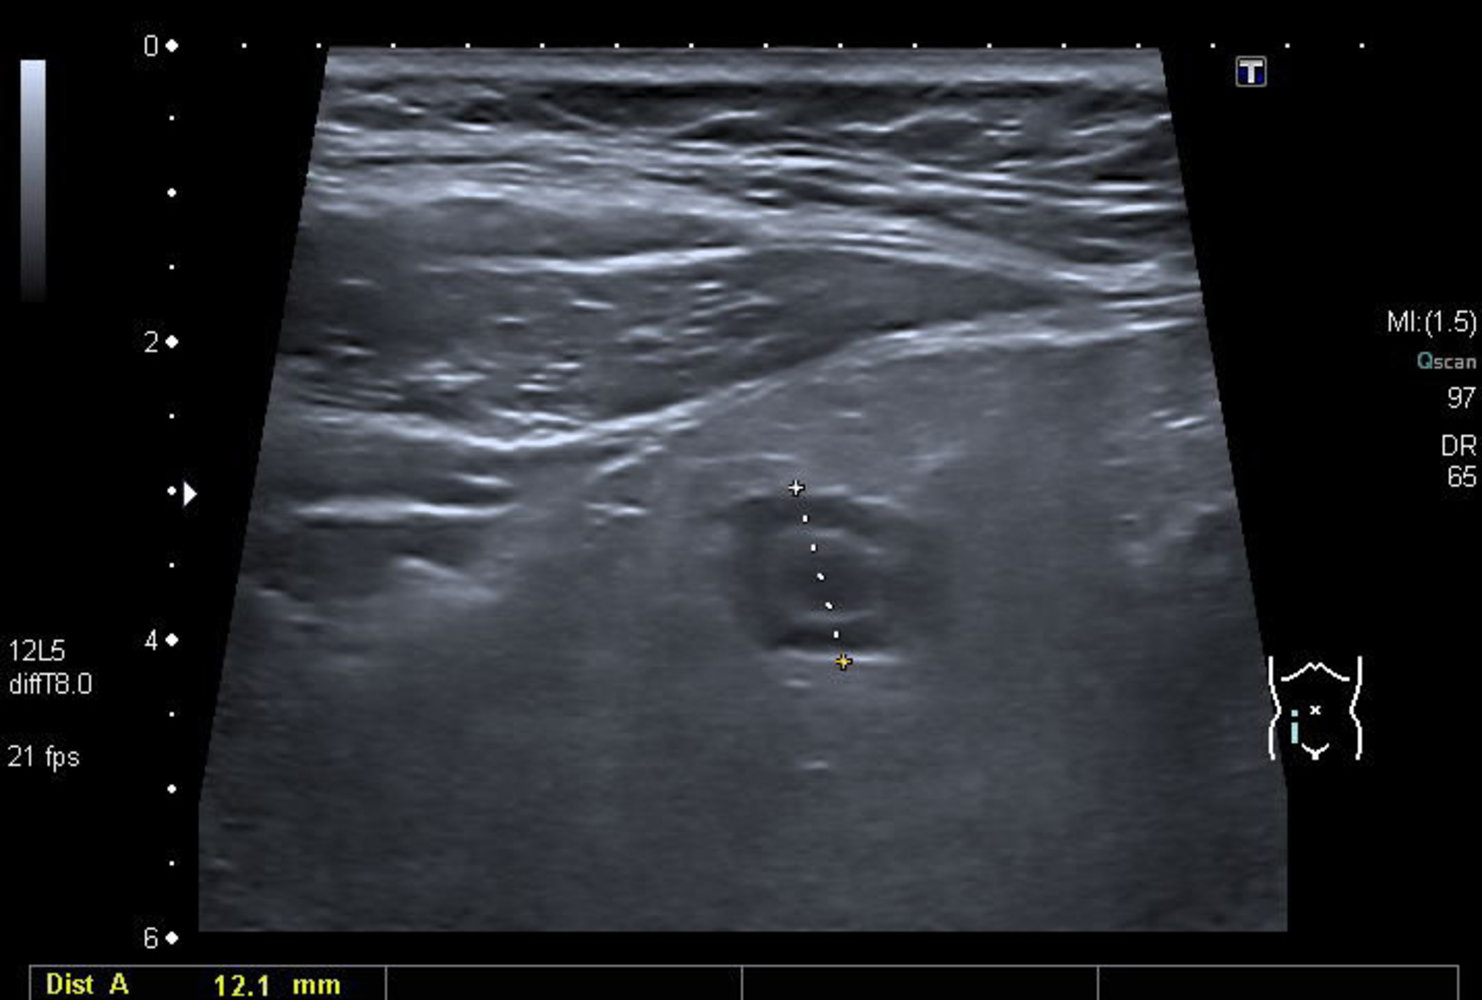

Abdominal ultrasound

Many institutions prefer ultrasound as the initial imaging modality, reserving CT scans for inconclusive ultrasound findings. [11][29]

Supportive findings [32]

- Distended appendix (diameter > 6 mm)

- Noncompressible, aperistaltic, distended appendix

- Target sign: concentric rings of hypo- and hyperechogenicity in the axial/transverse section of the appendix

- Possible appendiceal fecalith: focal hyperechogenicity with posterior acoustic shadowing

While abdominal ultrasound can confirm the diagnosis of acute appendicitis, normal ultrasound findings do not reliably rule out appendicitis. [10]